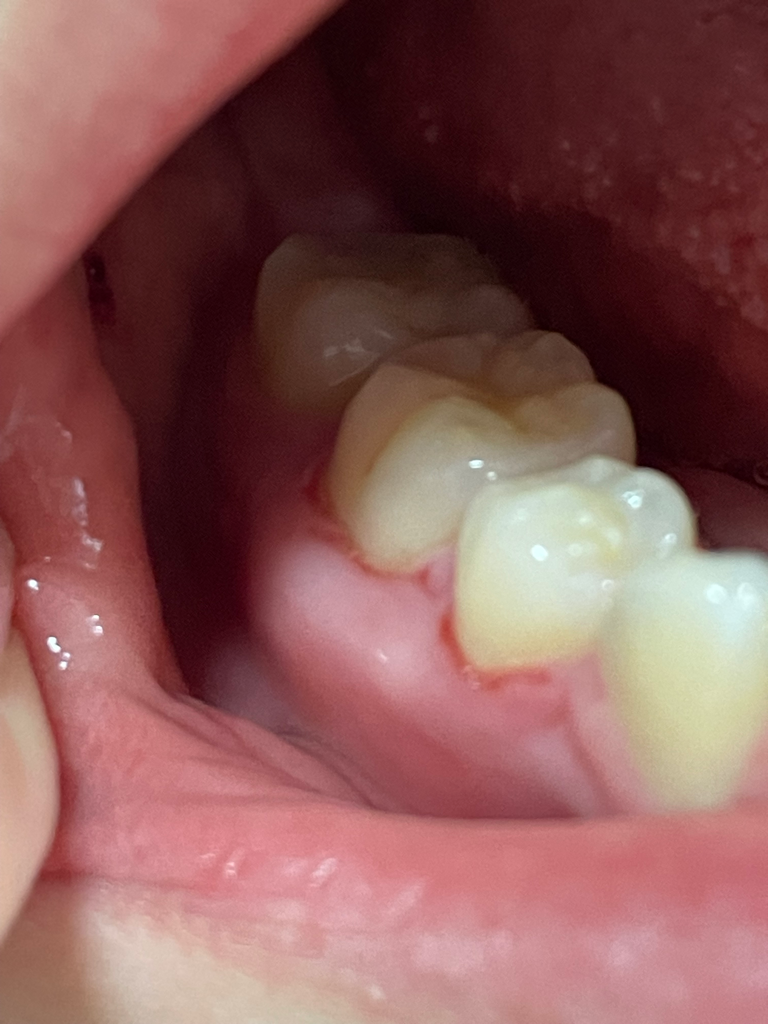

잇몸이 쓰리고 피나고 찢어졌어요??

교정할때부터 같은부위가 계속 이랬는데

교정때문인줄 알았는데 교정이 끝나간지 반년 다되가는데

또 같은자리에 잇몸이 피나고 양치할때 쓰려요

만졌을때 뼈만 있고 붓기는 보기에는 있어보이는데 실제로는 살이 붓거나 그런건없는거같고 그냥 뼈에요

치은쪽이 칼로 그은거처럼 찢겨있고 피가나요

위에도 어제부터 그러기 시작했는데 한 4일정도 되었구요

사진상으론 잇몸이 좀 부어있긴 합니다 치석은 없다하더라도 치과에서 스케일링 내지는 잇몸치료를 한번 받아보시고 경과를 지켜보는 것이 좋을 것 같습니다

양치를 너무 강하게 하시는게 아닌가요? 잇몸이 많이 부어 잇는것처럼 보입니다. 치과에 가셔서 잇몸치료를 받아보시는게 좋을것같습니다.

사진으로 보이는 형태는 잇몸에 자극이 너무 강하게 되어 상처가 난 것으로 보입니다.